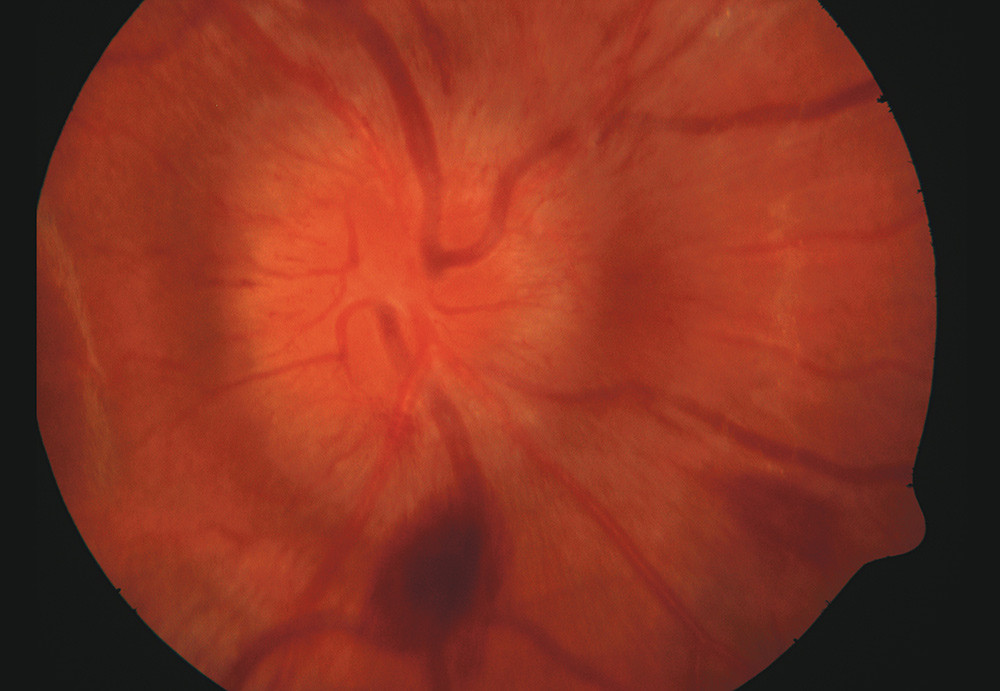

Flere uker senere ble pasienten igjen akutt dårlig, og det ble påvist nye cerebrale infarkter. Nå hadde han synsforstyrrelser, og det var defekter i synsfeltet på begge øyne. Ved øyeundersøkelse ble det påvist økende papillødem med ferske blødninger rundt papillen på begge øyne. Bildet viser papillødemet og blødningene på høyre øye. Vi har dessverre ikke bilder av perifer del av netthinnen. Pasienten ble også denne gangen bedre etter behandling med steroider og cyklofosfamid. En måned senere var papillødem og blødninger i retina forsvunnet, og det var kun en liten defekt i synsfeltet.